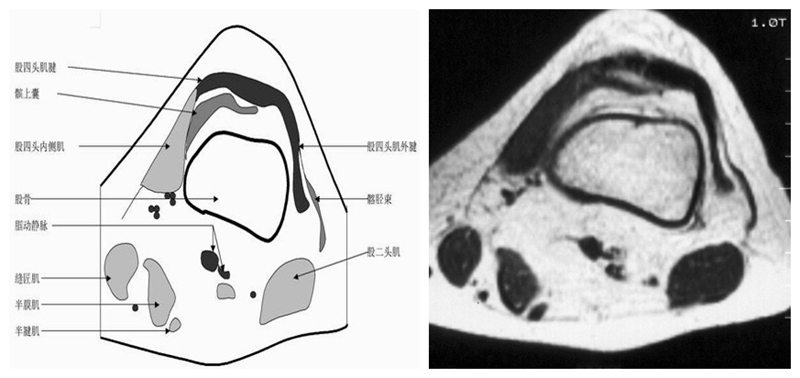

膝关节横断面MRI解剖

三维影像首选的方位,便于与CT比较,可准确地展现髌骨内外侧关节面。

横断面解剖第一层

横断面解剖第二层